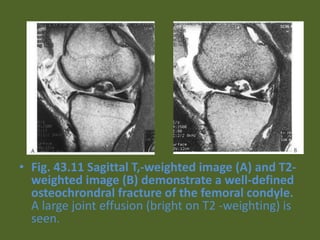

• Fig. 43.11 Sagittal T,-weighted image (A) and T2-

weighted image (B) demonstrate a well-defined

osteochrondral fracture of the femoral condyle.

A large joint effusion (bright on T2 -weighting) is

seen.

• Fig. 43.11Sagittal T,-weighted image (A) and T2- weighted image (B) demonstrate a well-defined osteochrondral fracture of the femoral condyle. A large joint effusion (bright on T2 -weighting) is seen.